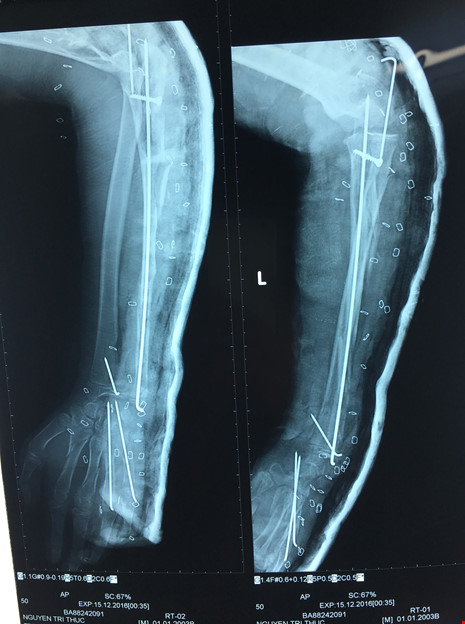

Tiếp theo, các BS nắn trật chỏm quay, cố định chỏm quay bằng kim. Đồng thời kết hợp xương dọc trục xương trụ, bắt vít cố định mỏm khuỷu, nắn xuyên kim cố định cổ tay, xương bàn ngón 4 và 5 tay trái.

Tay trái bệnh nhi T. sau khi phẫu thuật. Ảnh: VÕ KHÁNH